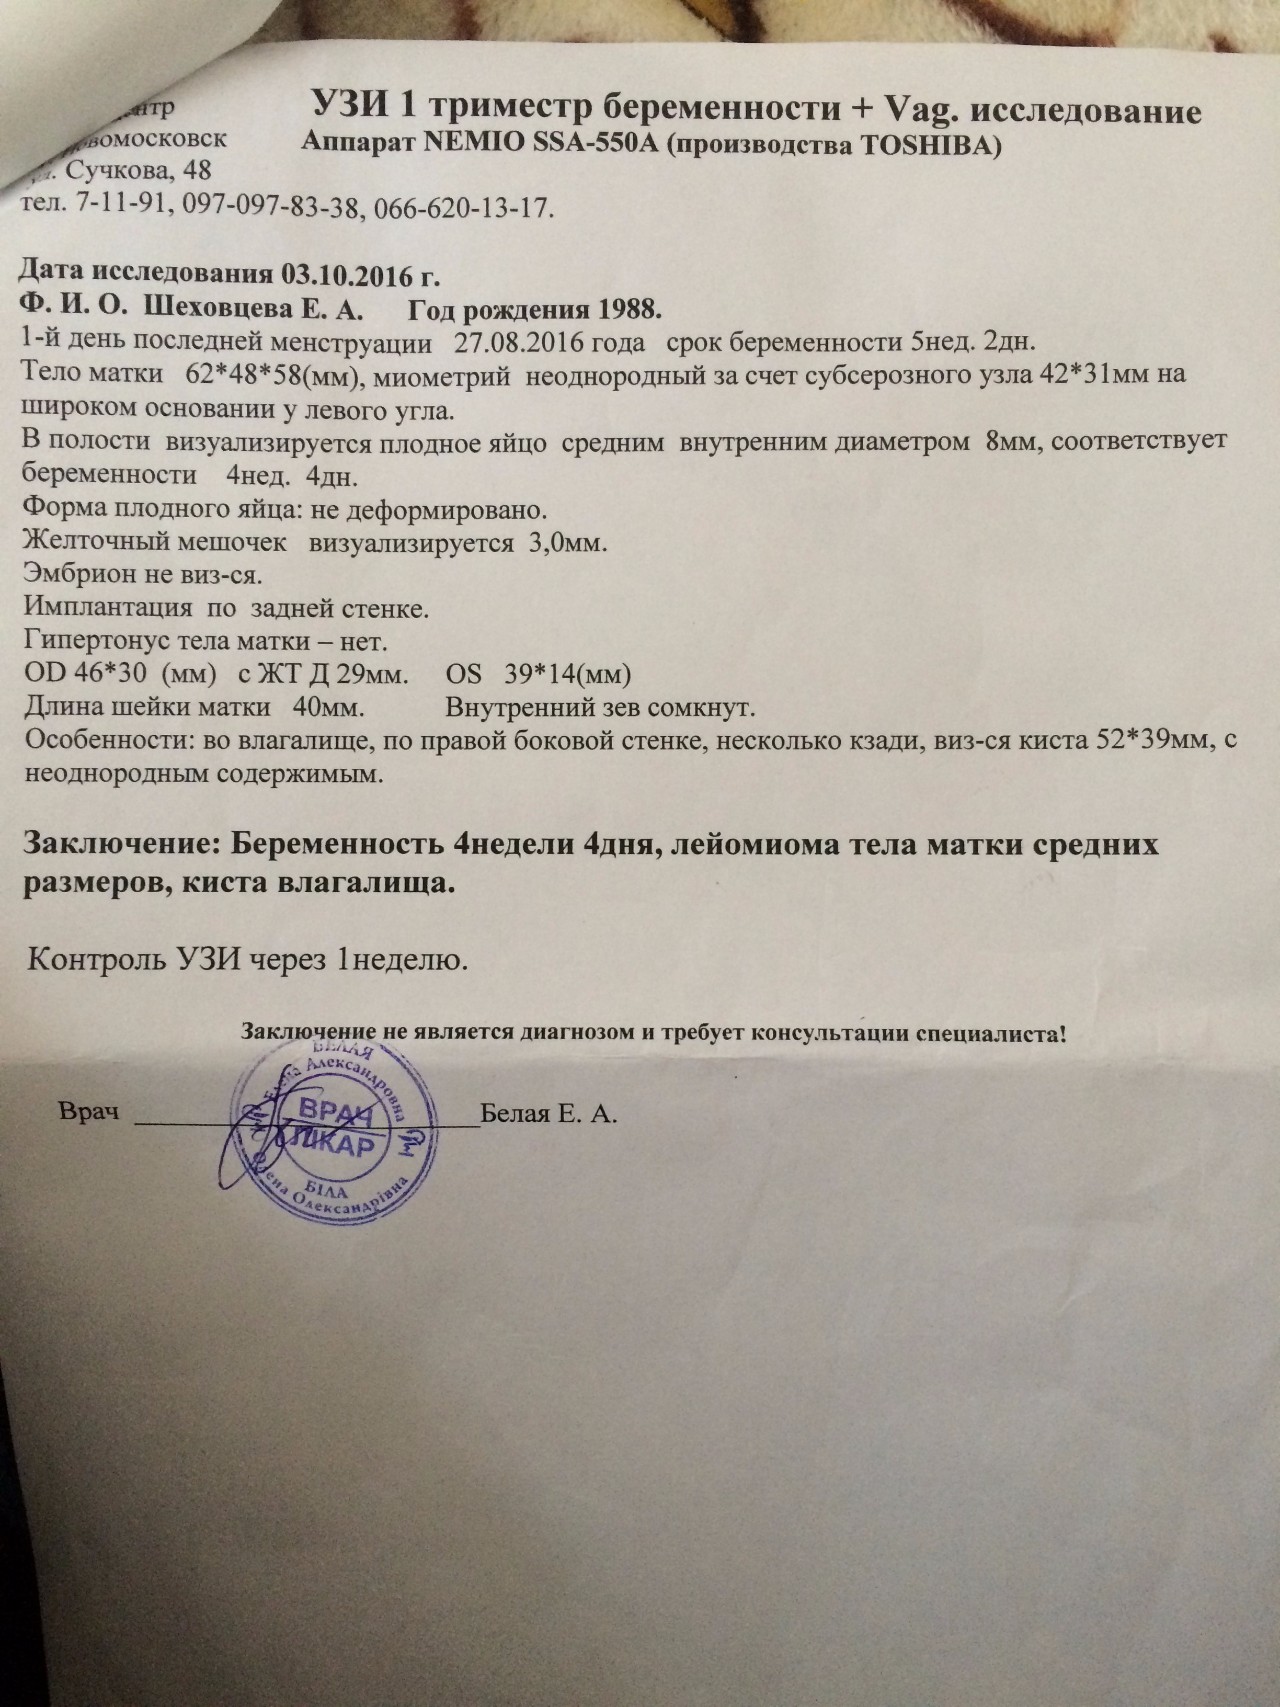

Маточная беременность 4 недели: особенности на УЗИ

На 4 неделе беременности ультразвуковое исследование помогает подтвердить маточную беременность, определить состояние плодного яйца и исключить возможные осложнения. Узнайте, как интерпретировать результаты УЗИ на ранних сроках.

УЗИ на ранних сроках беременности: когда делать, вредно ли, расшифровка

На 4 неделе может быть видно плодное яйцо, но эмбрион еще не всегда визуализируется.

Если УЗИ не подтверждает беременность, проконсультируйтесь с врачом для дальнейших анализов.

Повторное УЗИ может потребоваться через 1–2 недели для уточнения динамики беременности.